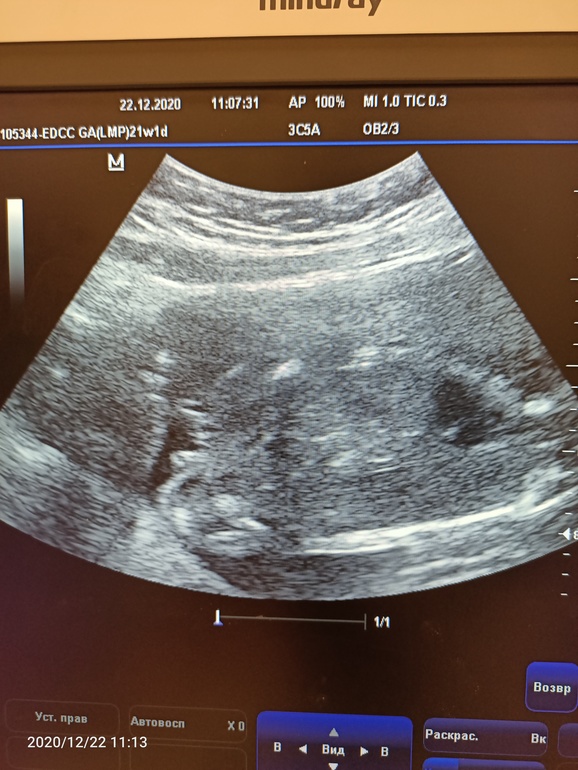

2 скрининг! 🌺

Волновалась я что-то перед скринингом, плохо спала ночью ( Но на УЗИ все волнения рассеялись) малыш такой чудесный, двигает ручками, гладит себя по лицу и носу 😅Пинал датчик 😅все показатели в норме) шейка 36, все закрыто 🙏

Пол узнать не удалось, так как мы очень активно вертелись, но предположили мальчишку 🙏

Всех с наступающим! Пусть ваши заветные желания и мечты исполнятся, а детки будут здоровы и счастливы! (приложила фотку, но не понятно на ней кто там, на девочку вроде не тянет) 😅

Это точно не лицо 😅 и вроде не Плацента. И не похоже на женский орган... Склонились к мальчику 😅

22.12.2020